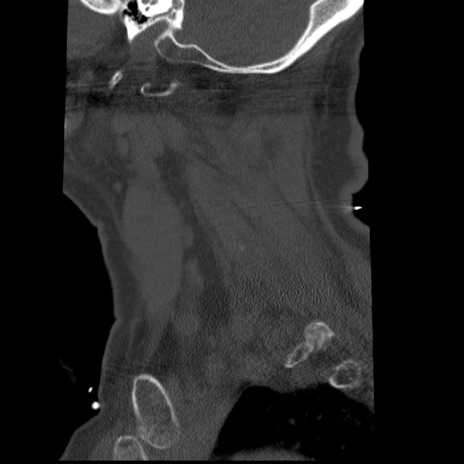

症例50 頚椎CT(矢状断像)

【症例】60歳代女性

【主訴】後頭部〜右後頸部にかけての痛み

【現病歴】本日飲食店でコーヒーを飲んでいたところ、突然後頭部〜右後頸部にかけて痛みが出現し、右上肢の感覚障害を伴ったため救急要請。

【身体所見】脳神経学的に明らかな異常所見を認めず。右上肢に軽度の感覚障害あり。

異常所見と診断は?